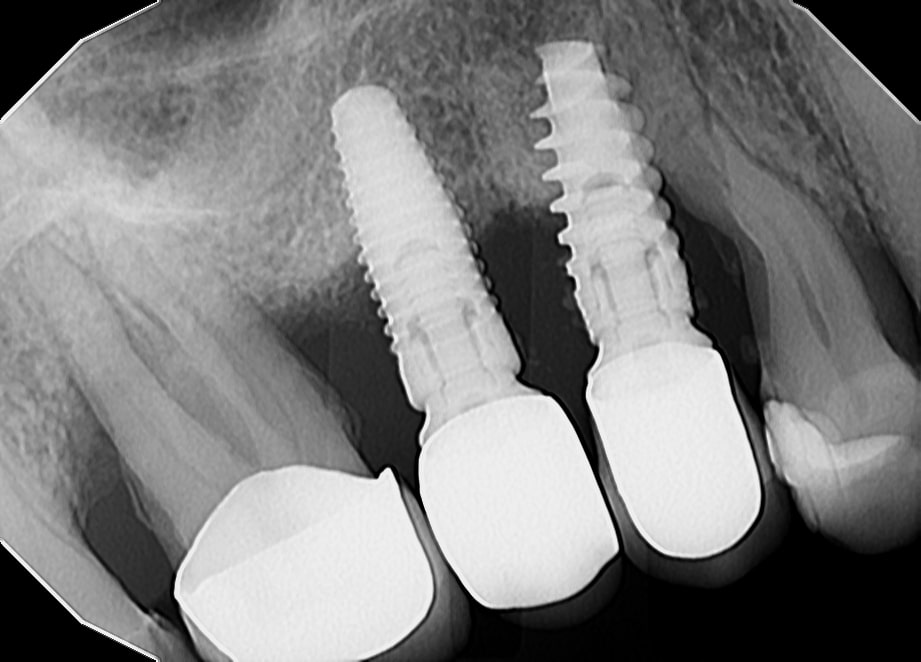

Periimplantitis je upalno patološko stanje koje zahvaća tkiva u neposrednoj okolini dentalnog implantata, pri čemu dolazi do upale periimplantatne sluznice i postupnog gubitka koštanog potpornog tkiva. Kliničke manifestacije periimplantitisa uključuju upalu, krvarenje pri sondiranju, supuraciju, povećanu dubinu sondiranja i gubitak kosti (Slika 1.). Upala mekih tkiva obično se otkriva krvarenjem pri sondiranju, dok se gubitak kosti prepoznaje na radiografskim snimkama kao ˝krater˝ oko implantata uz povećane dubine sondiranja (Slika 2.). Dubina sondiranja može ukazivati na ozbiljnost bolesti i korelira s gubitkom kosti, čija brzina varira među pacijentima (1). Periimplantitis se često razvija kod pacijenata s prethodnom anamnezom uznapredovalog parodontitisa, lošom kontrolom plaka te nedostatkom redovite terapije održavanja nakon implantološkog zahvata.